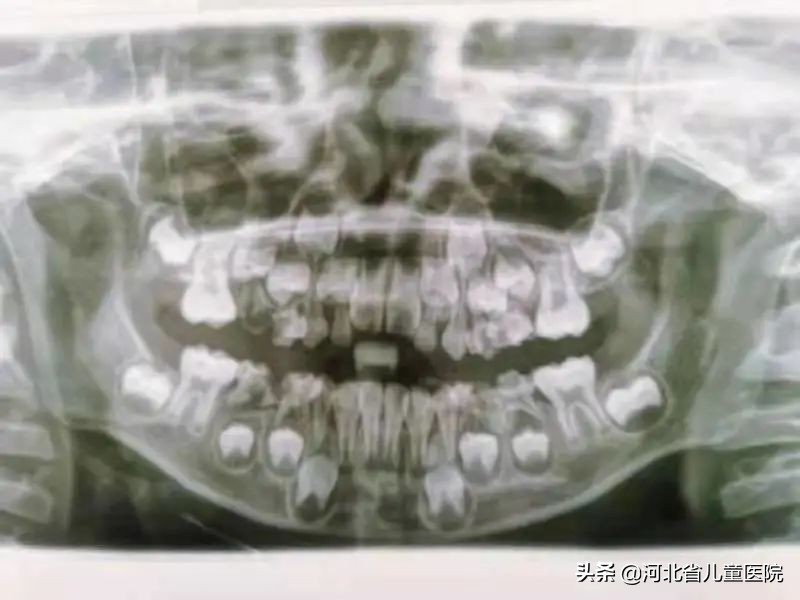

7岁的星星是一位极重度再生障碍性贫血患儿,在计划进行造血干细胞移植术前,为排除移植治疗风险前来口腔科会诊检查。检查发现患儿多颗牙齿存在慢性根尖炎症等问题,根尖感染严重的乳牙可能增加移植感染的风险,需要进行根管治疗或者拔除。

患儿血液检查时白细胞、血小板、血红蛋白及红细胞均减少,出血时间及凝血时间也延长,拔牙后可能有出血不止的风险。口腔科与血液科经讨论后,采用血小板输注、压迫止血及药物止血等方式,分次对患牙进行了乳牙根管治疗及乳牙拔除,术后患儿创口区成功止血,无感染发生。